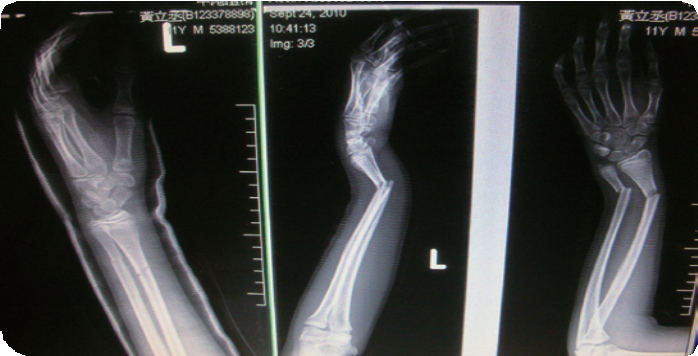

2010年9月24日早上第一节下课时,照惯例一定要和同学出去打球动一动,就在抢球一瞬间,满脑子想着冲啊冲啊的我,不小心绊到同学的脚,结果这一摔,不只是单纯的跌倒而已,当我回过神,前手臂已经严重变成V形,还听到喀喀两声,周围的同学疯狂大喊着:「啊~完了,骨折了!」

当时在急诊室里,手一直痛起来,而爸妈正在赶来的路上,我忍着痛在心里跟主耶稣祷告,恳求主耶稣不要让我的手断得很严重……。在看到妈妈时,我眼眶红了起来却不敢哭,因为怕妈妈担心……。等了好久终于轮到我,医生先安排我照X光,然后在急诊室我有了自己的病床,但因那一天急诊室有很严重的车祸病人,等了好久才轮到我照X光,照完才终于可以舒服地躺在病床上暂时休息……。

下午三点,我准备动手术,外婆先带我在旁边祷告,心里本来很紧张,祷告完心里平静许多,妈妈哽咽地跟我说要勇敢,主耶稣会保护我,我跟妈妈说不用担心,我会在心里一直跟神祷告。进手术室前,医师先跟我们解释整个手术过程,进了手术房,我还不忘跟医师说,我想要保存X光片,医师说没问题,麻醉针打完之后,我就昏昏沉沉地睡着了……。

当我从恢复室醒来时,一直以为还没动手术,大声的问护士阿姨开刀了吗?我肚子好饿哦……。见到妈妈才知道,原来我并没有动刀,医师只有徒手帮我复位,因为复位顺利,并不需要上任何钢钉或钢板。